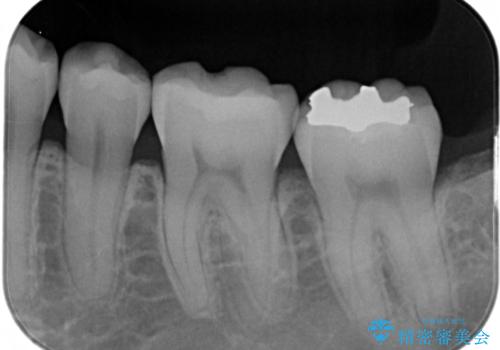

- 矯正治療が終了して歯並びが綺麗になると、元々入っていた銀歯が気になってきたとのことで適合の良いセラミックへのやり替えを行いました。

適合不良の補綴物は二次的な虫歯発生のリスクが高まります。

自費診療で用いられる材料は保険適応の材料に比べて、より精密で適合の良い被せ物作ることができるため、長期的な虫歯のリスクを大幅に減らすことが可能です。